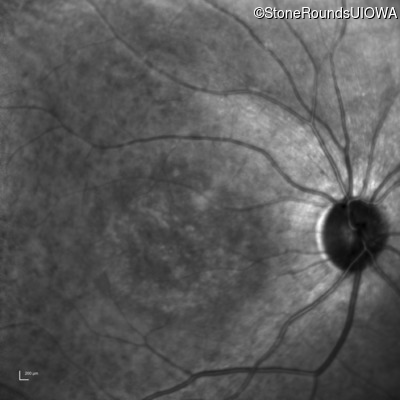

Infrared Fundus Photograph - Right - 20/200 -3

Exemplar

Infrared Fundus Photograph - Left - 20/200 -2